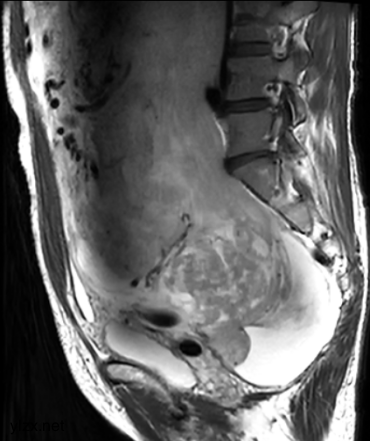

MRI检查:

子宫右侧巨大实性占位,大小约260×110×91mm,与子宫分界不清,T1WI呈稍低信号,T2WI呈不均匀稍高信号,呈束状、旋涡状改变(图1),病变内部分可见囊变,肿瘤内部及表面多发流空血管影(图2);DWI上病变呈略高信号,ADC图呈略低信号,ADC值为1.633×10-3 mm2 /s;增强扫描呈明显强化(图3),内部见条片状低信号。影像学考虑子宫右侧恶性肿瘤。

图1

图2

图3

子宫PEComa影像学表现各异,其MRI表现具有一定的特征,肿瘤T2WI信号稍高,呈束状排列,富血供,可伴有变性、坏死,肿瘤内部及表面可见多发流空血管影。